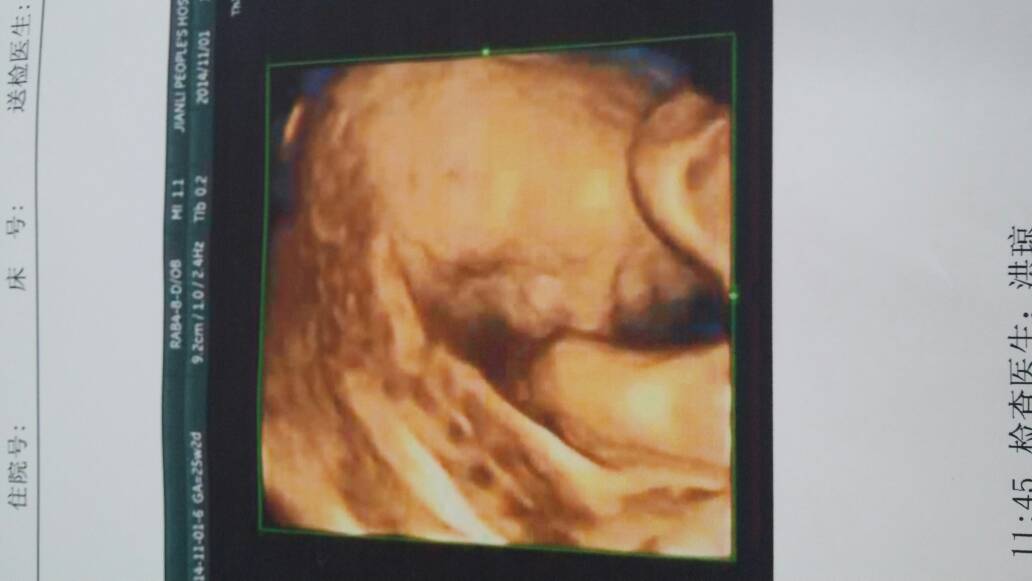

今天照的各位宝妈帮忙看下 今天照的各位宝妈帮忙看下 点击展开 默规 2014-11-01 12:30 为您推荐: 其他回答 你好,看图片是宝宝的颜面部的照片的。按时产检,祝你生个 健康的宝宝 文斯6 2014-11-01 21:50 我那天也是,害我爬了几趟楼梯 准妈豆豆 2014-11-01 19:20 挺好的,,, 简单的妈妈 2014-11-01 17:55 宝宝侧面, 准妈豆豆 2014-11-01 12:50 宝宝很可爱哦,看上去像一个男孩子,只是猜测一下而已,不准的哟 爱你宝贝儿2014 2014-11-01 12:44 加载更多 相关问题 各位宝妈,帮帮忙,我家女儿今天晚上发烧四十度,跑去医院不给看,说烧了三天在来,请问各位宝妈,有什么 宝宝现在四个半月了,今天下午发现下嘴唇中间有点发黑是什么原因,有知道的宝妈告知下